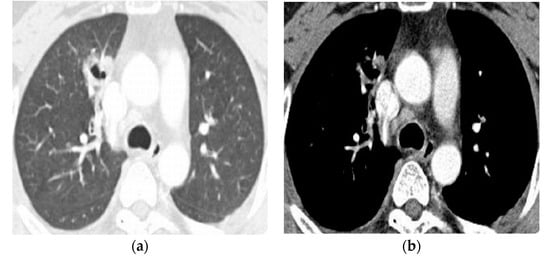

The CT findings of pleuropulmonary paragonimiasis are summarized in Table 3. Of the 103 patients, 91.3% (94/103) were available for an analysis of the location and distribution of the lesions. The main pulmonary lesions were located in the upper lobe in 57.4% (54/94) (Figure 1a,b), in the lower lobe in 35.1% (33/94), and in the right middle lobe in 7.5% (7/94) (Figure 2a,b), with a peripheral distribution in 77.7% (73/94), a central distribution in 13.8% (8/94), and both in 8.5% (3/94). Nodular opacities on CT scans were the most common findings (53/94, 56.4%). By analyzing the patterns of nodules, non-cavity nodule and cavitary nodules were reported to be 59.6% (31/53) and 40.4% (22/53), respectively. The sign of worm migration tracks, known as one of the typical findings of pleuropulmonary paragonimiasis, was only present in 18.1% (17/94) of patients. The mean length and diameter of worm tracks were 19.7 mm and 5.3 mm, respectively (Figure 3a,b) Although the initial CT showed no statistical significance between the group with correct diagnostics and the group with incorrect diagnostics, in the case of a correct diagnosis, the number migrating worm track was high (12/17, 70.6%), and in the group showing incorrect diagnosis, air-space consolidation (18/25, 72%), and mass (6/8, 75%) were high.

Figure 1.

A 41-year-old woman was admitted to an emergency room with a chief complaint of persistent cough, presenting with eosinophile counts of 14.4 %. Chest CT scans of the lung (a,b) show a focal consolidation with a migration worm track in the right upper lobe. The patient was initially diagnosed with pleuropulmonary paragonimiasis on CT scans, whose findings were positive in the enzyme-linked immunosorbent assay (ELISA).